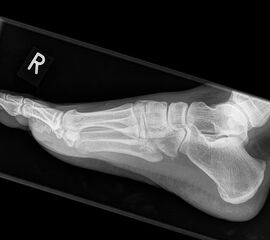

Fuß seitlich mit Belastung

Positionierung:

• Der Patient steht auf beiden Füßen mit gleichmäßiger Lastverteilung.

• Der zur Röntgen der Fuß wird längs des Films positioniert.

• Die Kassette steht senkrecht zum Boden, medial dem Fuß anliegend.

• Der Zentralstrahl wird von lateral nach medial zentriert auf das Kalkaneokuboidalgelenk knapp cranial der Os metatarsale V Basis ausgerichtet.

• Die Röntgenröhre steht 0° horizontal.

Kennzeichen des Röntgenbildes:

• Standardabbildung des Fußes zusammen mit der belasteten d.-p. Aufnahme und der unbelasteten 45° Pronationsaufnahme.

• Überblick über die Fußanatomie und Fußstatik.

• Die seitliche Aufnahme liefert Informationen zur Stabilität des Längsgewölbe und zu den Achsen von Talus, Kalkaneus und Metatarsale I.

• Die Aufnahme wird eingesetzt zur Darstellung von freien Gelenkkörpern sowie knöchernen Veränderungen am Achillessehnenansatz oder der Plantarfaszie.

Besondere Bemerkungen zum Beispielbild:

• Schwere Hallux valgus Deformität.

• Die Sesambeine sind luxiert, ebenso das Großzehengrundgelenk. Luxation des Metatarsophalangealgelenks II.

• Degenerative Veränderungen der tarsometatarsalen (TMT) Gelenkreihe, betont TMT II und III.